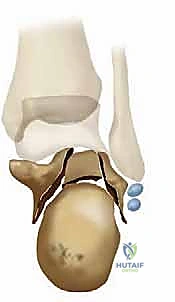

تُظهر الصورة أعلاه فحصاً بالأشعة المقطعية يوضح مدى تعقيد الكسر الأولي والإزاحة التي تحدث، مما يسلط الضوء على التشريح الفوري بعد الإصابة والذي يمهد لسوء الالتئام إذا لم يُعالج بدقة.

المفصل تحت الكاحل هو مفصل زلالي معقد يسمح بحركتي الانقلاب الداخلي (Inversion) والانقلاب الخارجي (Eversion). أي خلل في تطابق الأسطح الغضروفية لهذا المفصل بمقدار ملليمترات قليلة يؤدي إلى احتكاك غير طبيعي، تآكل سريع للغضروف، وتطور التهاب المفاصل التنكسي (Osteoarthritis) المؤلم.